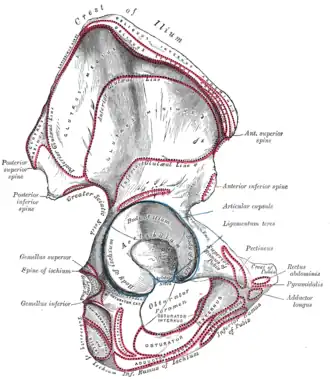

Right hip bone. External surface.

Right hip bone. External surface. -

Hip joint. Lateral view. Acetabulum.

-

Hip joint. Lateral view. Acetabulum.